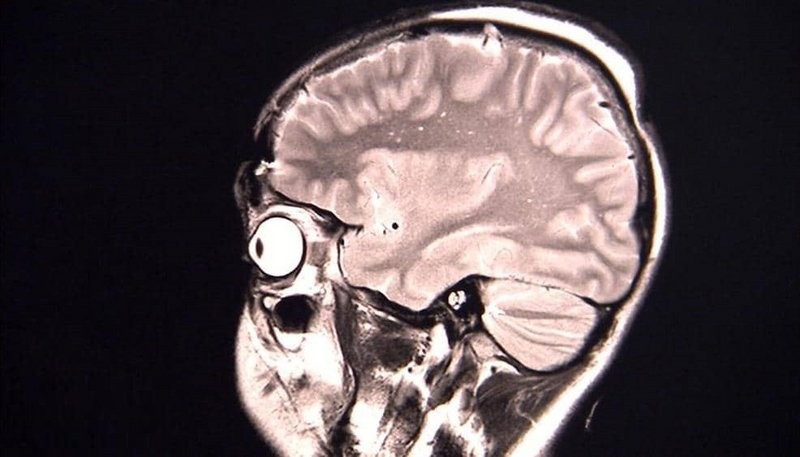

ورغم أن ثلاث حالات ليست كافية للوصول إلى استنتاجات على نطاق واسع بشأن الوباء، إلا أن العلماء يعتقدون أن الأعراض ربما تكون نتيجة للاستجابة المناعية التي تسبب التهاباً في أجزاءٍ معينة في الدماغ.